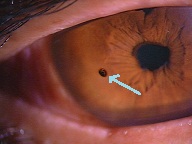

?黄斑円孔で、赤の部分の網膜が硝子体に引っ張られて断裂し、無くなってしまうと、視野の中心部が欠損、見たい部分が見えなくなってしまいます。

⇒手術前の穴が、大きければ大きいほど術後の回復が悪く、穴が小さければ小さいほど良好な回復が得られます

黄斑円孔の手術後の回復の程度や見え方は、円孔の大きさや、発症からの時間、年齢など、様々なものが関与するため、一概には言えないのですが、完全な元通りを期待するものではないことはご理解下さい。

中心部の視野がごくわずか。

中心部の視野がごくわずか。